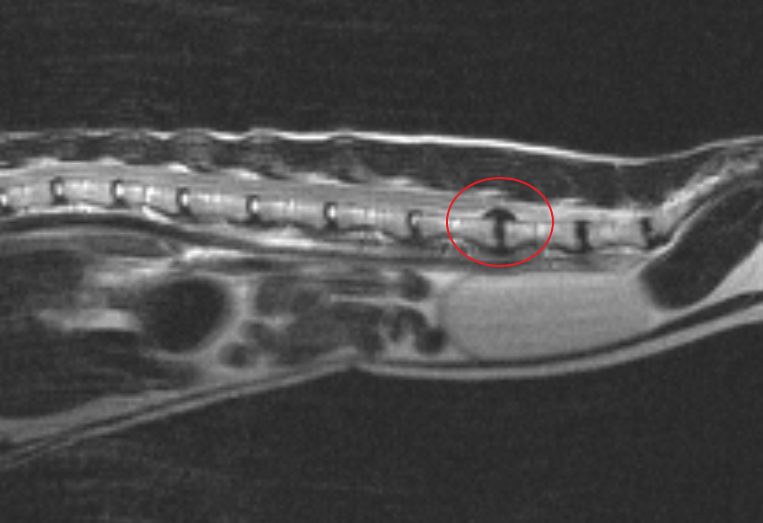

При межпозвоночных грыжах в грудном и поясничном отделах (рисунок 1), мы проводим операцию под названием «минигемилламинэктомия» (приставка «мини» означает, что операция менее инвазивна и мы не удаляем отростки позвонка, как это делается при гемиламинэктомии).

Рисунок 1 – Экструзия межпозвоночного диска у кота в поясничном отделе